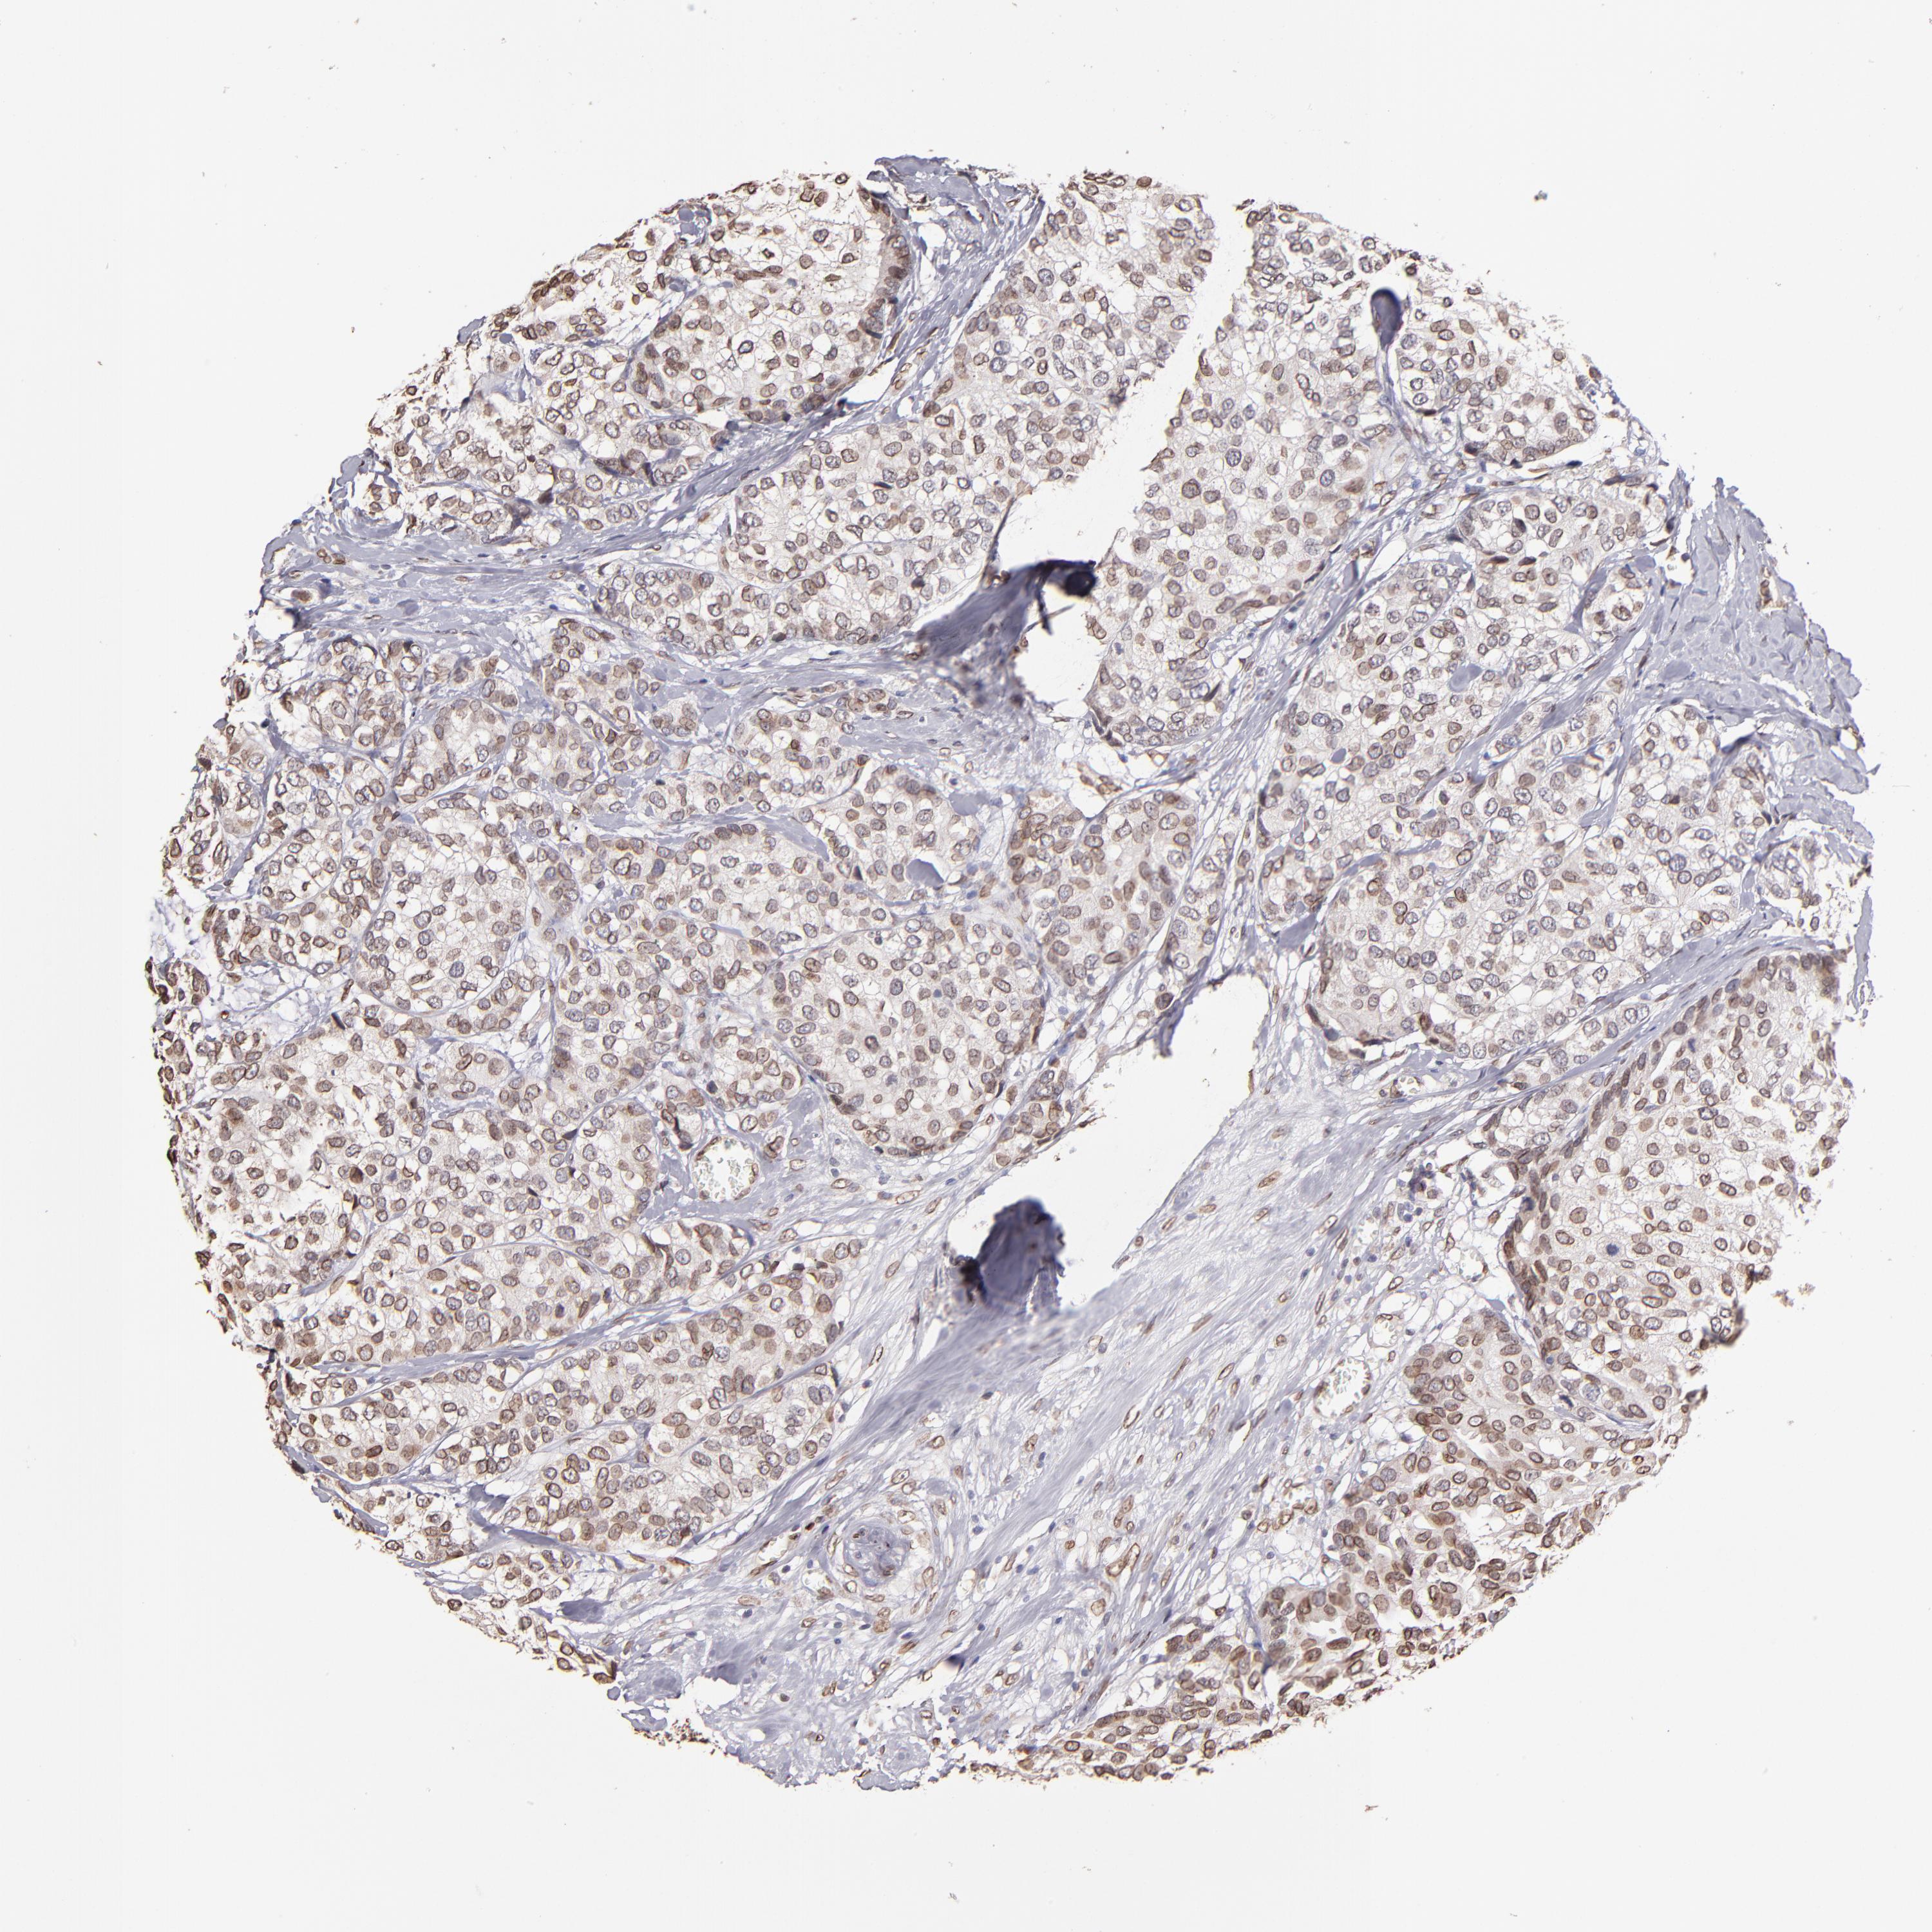

BRCA TCGA BRCA VALIDATION PROTEIN EXPRESSION